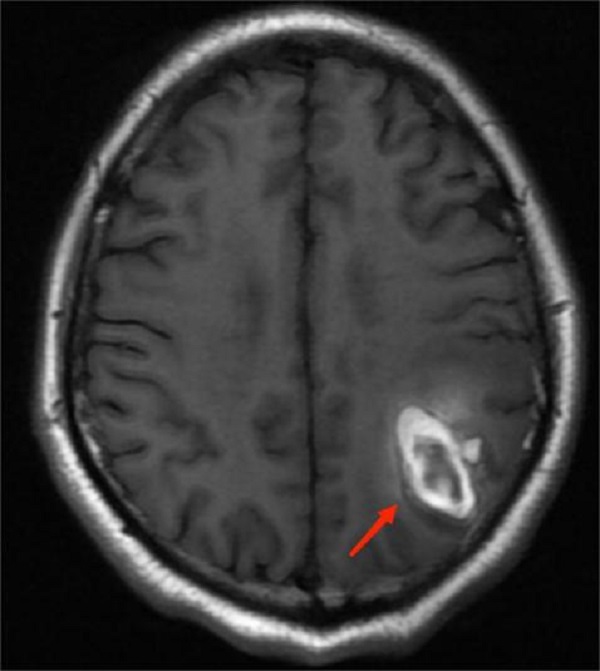

日前,由四川大学华西医院游潮教授团队和澳大利亚乔治全球健康研究院共同发起的急性脑出血国际多中心研究的重大研究项目,INTERACT3总结大会在成都举行,陕西省核工业二一五医院作为陕西省内唯一一家参加该项目的...

为进一步推动咸阳市各县区脑血管病诊疗技术水平的发展,7月22日,陕西省核工业二一五医院成功举办了咸阳地区脑血管病沙龙。来自咸阳各县区脑血管病相关专业负责人,咸阳市辖区内神经内外科学者参加。会议由二一五...